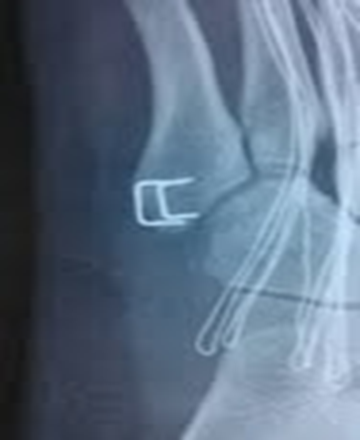

微型钩钢板固定——一种新的有效手术方法适用于第五跖骨基底部I区和II区骨折(移位﹥2毫米)或者伴有小的粉碎型撕脱骨折块。

第五跖骨基底骨折应用钩钢板固定法治疗更为牢固可靠,且应力性能好;对于粉碎骨折、移位较明显的骨折,钩钢板法尤其具有明显优势,钩钢板的尖头钩可牢固抓持粉碎骨块,实现可靠复位,能更有效缩短患者住院时间、促进骨折愈合、恢复患足功能、促进早期功能锻炼,疗效显著且安全性高,是治疗第五跖骨基底骨折的一种安全有效的方案。

设计:微型管状的钩板的最后一个孔被设计成可充当用于压缩作用的钩,抓粉碎骨折块,防止移位,并且在基底部可以控制旋转稳定。